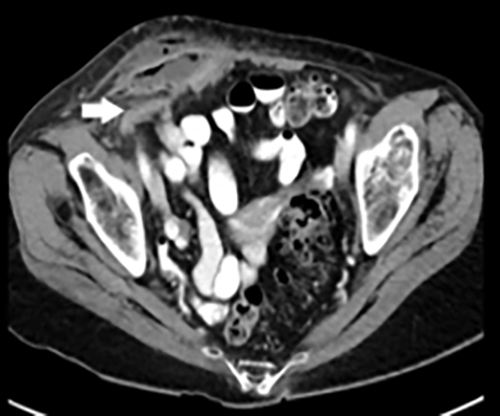

We describe the case of an 84-year-old female presenting with a right Amyand’s hernia containing a perforated appendix and a large associated abdominal wall abscess. Her medical history includes hypertension, dementia, and no prior surgical interventions. She presented to the emergency department with a one-week course of progressive right lower quadrant pain, nausea, and chills. During the initial evaluation, she was found to be febrile. Her physical exam noted right lower quadrant tenderness with overlying skin erythema and fluctuance to palpation. A computed tomography (CT) of the abdomen and pelvis showed an incarcerated, perforated appendix coursing into the right inguinal canal with an adjacent 6.9 × 4.5 × 7 cm abdominal wall abscess. She was admitted to the hospital for intravenous antibiotic treatment and percutaneous drainage of the abscess by interventional radiology. The abscess culture grew Escherichia coli and Streptococcus anginosus. On hospital day 10, she was discharged to a nursing facility for drain care, where an oral course of amoxicillin-clavulanate for 14 days was completed. Approximately one month later, the patient returned to the operating room for an interval laparoscopic appendectomy. Upon exploration of the abdomen, the appendix was found to be incarcerated within the right inguinal hernia. Once successfully reduced, a standard laparoscopic appendectomy was completed. No fluid collections were evidenced in the abdomen or abdominal wall. A large right inguinal defect was visualized, and the decision to pursue a definitive hernia repair at a later stage was made, given her high risk for mesh infection. Her postoperative course was uneventful. During her postoperative follow-up, her son and heath care proxy decided not to pursue hernioplasty, given her recent functional decline and high morbidity risk.

Figure 2. Abdominal Wall Abscess Measuring 6.9 × 4.5 × 7.0 cm. Published With Permission